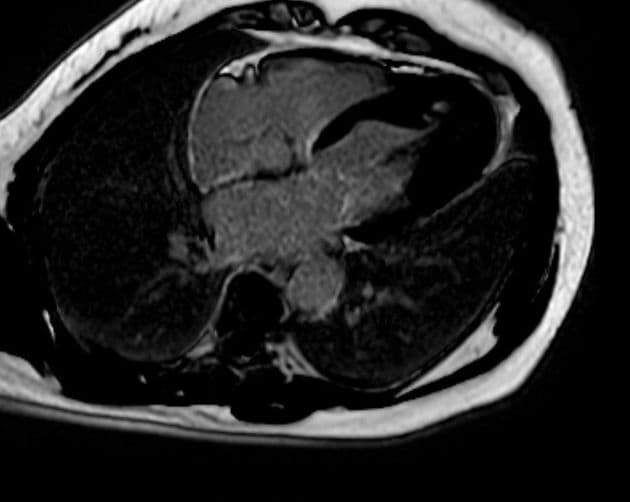

- Không thấy huyết khối (thrombus) trên hình gadolinium sớm, và không thấy tăng quang cơ tim (myocardial hyperenhancement) trên hình gadolinium muộn.

- Trên cộng hưởng từ (MRI), các phát hiện điển hình gồm phù cơ tim (myocardial edema) và không có thiếu máu cục bộ (ischemia) hay xơ hóa (fibrosis), điều này được chứng minh bằng việc không tăng quang ở thì muộn sau tiêm gadolinium (lack of enhancement at late gadolinium imaging).

- "Việc không thấy tăng quang muộn ở thì tiêm gadolinium trên cộng hưởng từ tim giúp phân biệt bệnh cơ tim Takotsubo với nhồi máu cơ tim hoặc viêm cơ tim."

Bệnh cơ tim Takotsubo, còn gọi là bệnh cơ tim do stress, đặc trưng bởi rối loạn chức năng thất trái tạm thời do stress về mặt cảm xúc hoặc thể chất, thường gặp ở phụ nữ sau mãn kinh. Mặc dù thể 'phình đỉnh' cổ điển là phổ biến nhất, các thể bất thường như thể giữa thất, thể đáy và thể hai thất ngày càng được nhận biết rõ. Trường hợp này biểu hiện thể giữa thất với rối loạn vận động của thành trước giữa và phù cơ tim trên cộng hưởng từ, nhưng không có dấu hiệu nhồi máu hay xơ hóa. Việc không thấy tăng quang muộn là điểm phân biệt quan trọng với tổn thương do thiếu máu. Diễn tiến lâm sàng với cải thiện tự phát trong vài tuần khẳng định chẩn đoán. Nhận biết các biểu hiện bất thường này là rất quan trọng để tránh chẩn đoán nhầm thành hội chứng vành cấp.